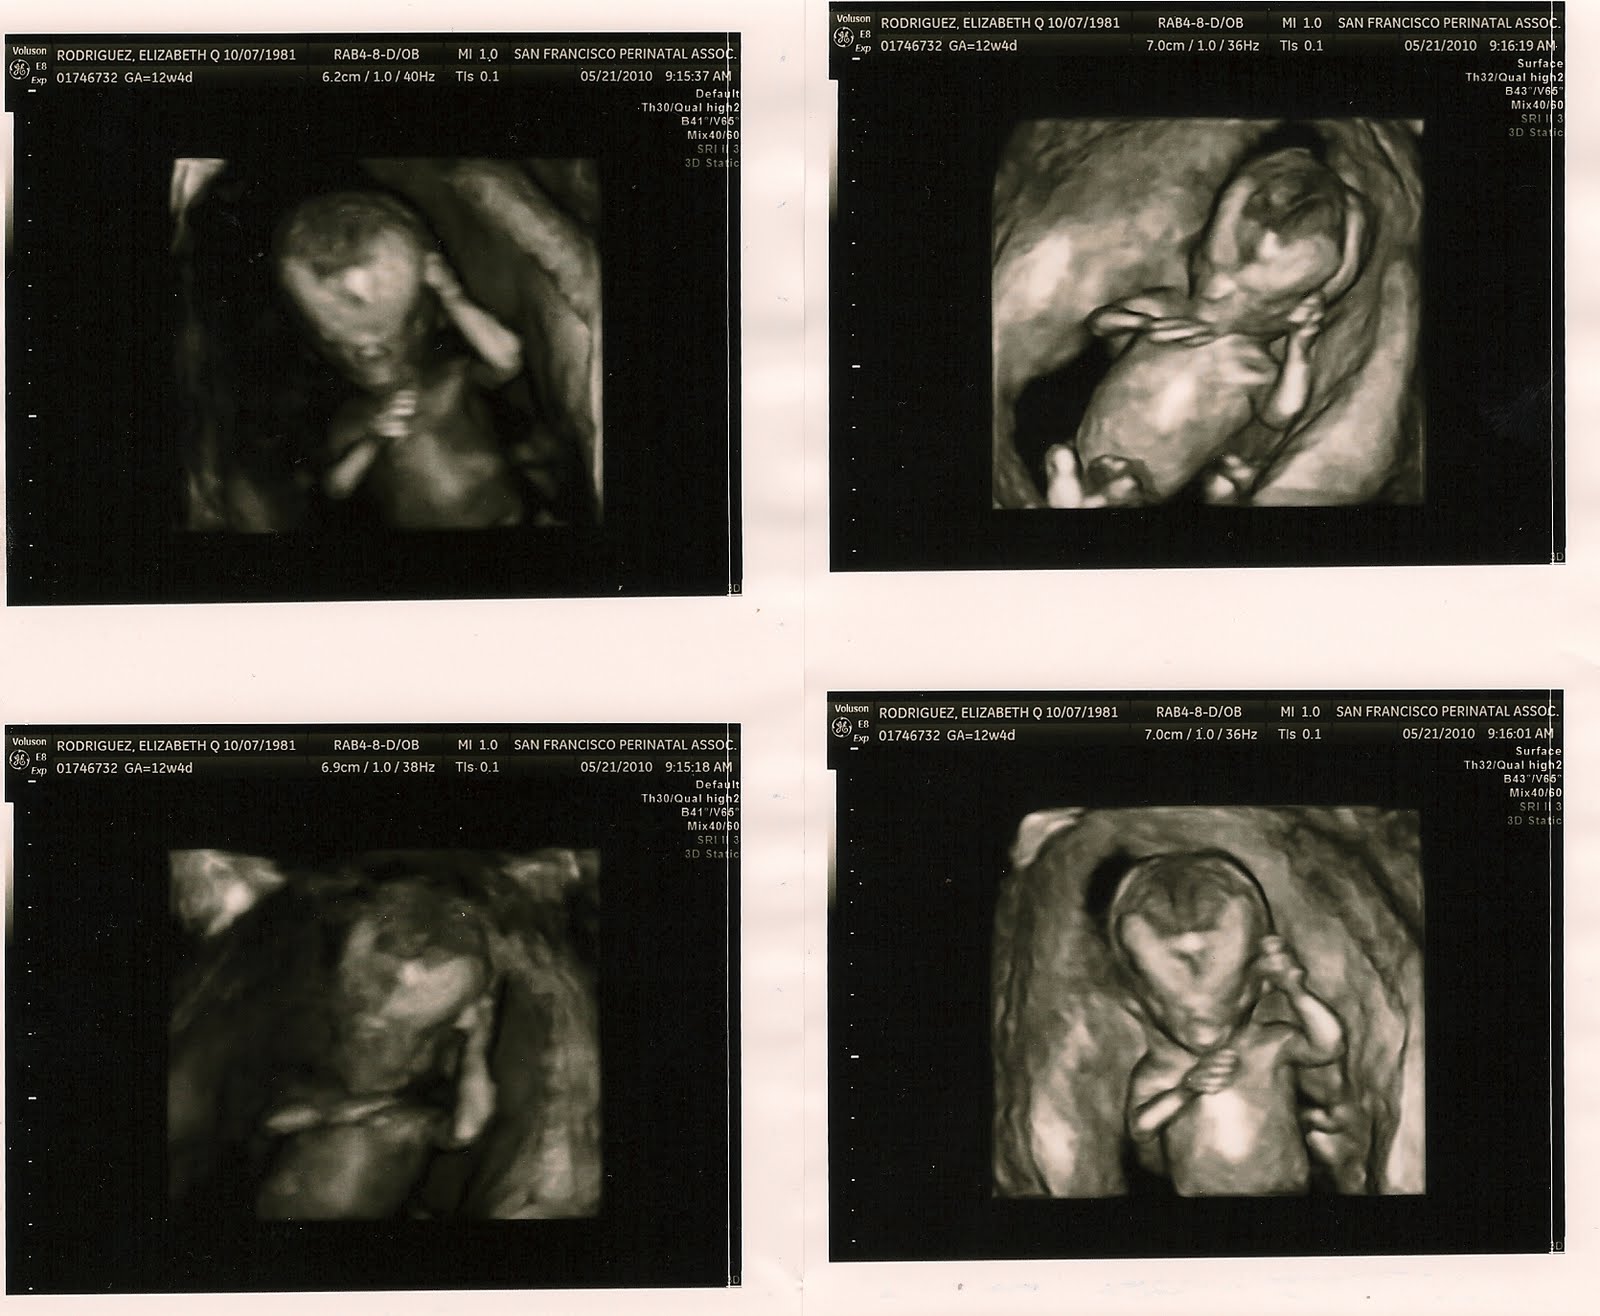

Back to the most important thing in the world, life! Today was my integrated screening, I've been waiting for this for sooo long!!!!! I popped out of bed at 5am, ready to go by 7am, and had to chillax by the time our appt came around at 8:30am, lol. Seeing our baby actually look like a baby was surreal! It was the first appointment where I didn't cry hysterically because I was taken aback by my baby's beautiful dancing/ballet, it was my first proud mommy moment! My husband and I tried to zone in on our baby's genitalia, but couldn't see a thing since baby's legs were crossed the majority of the time. I have a feeling it's a girl... either way I'm elated since the chance baby has down syndrome is 1 in 30,000, woohoo!!!

Alright, so more fun stuff- pics!!! I have to cut this blog short due to the fact that I have to finish packing the rest of the apartment and study some more for my final tomorrow ;)

Look at my beautiful baby sucking it's thumb :')

12w4d!!!